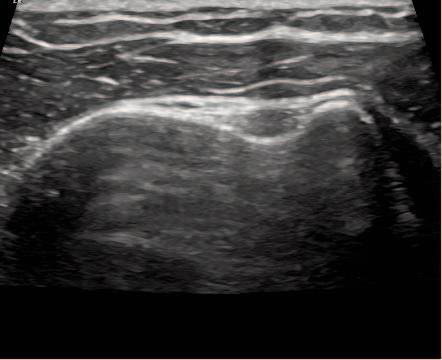

Figure 2b: Normal Tendon-Long Axis View.

LHBT is seen running parallel along the image running proximal to distal from left to right. It should be seen as a bright hyperechoic fibrous band of tissue.The deltoid is seen above as a linear tissue with darker muscle bundles.

Figure 3b: Joint effusion within the tendon sheath seen here on the LAX. On the LAX views, it reveals presence of fluid distally indicating a tenosynovitis. A capsulitis would not show effusion in the biceps tendon sheath distally on the LAX view.